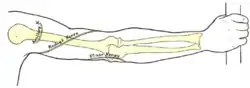

Nerves of the left upper extremity. (Ulnar labeled at center left.) | |

Front of right upper extremity, showing surface markings for bones, arteries, and nerves. Back of right upper extremity, showing surface markings for bones and nerves.

Back of right upper extremity, showing surface markings for bones and nerves. Ulnar nerve